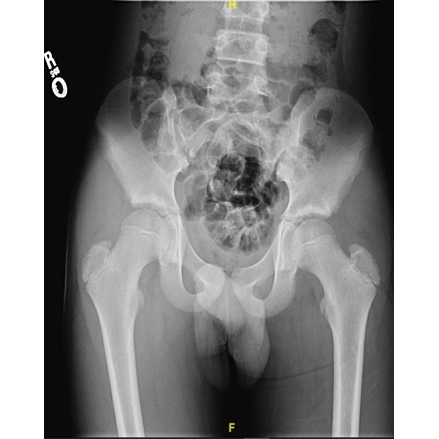

In the emergency department, an x-ray of his right hip and pelvis showed a well-preserved hip without acute fracture Case Photo #1 Case Photo #2 . An ultrasound of his right hip did not show a joint effusion in both transverse and longitudinal views Case Photo #3 Case Photo #4 . On admission, an MRI of his right hip and pelvis without contrast showed asymmetric right hip joint fluid Case Photo #5 . This was thought by Radiology to be within normal limits for his age. Due to an up-trending fever curve, up-trending inflammatory markers, and worsening pain by hospital day 2, an MRI of his right femur with contrast was obtained. It showed an increased small right hip joint effusion, however there was no evidence of myositis, osteomyelitis, or osseous lesions Case Photo #6 .